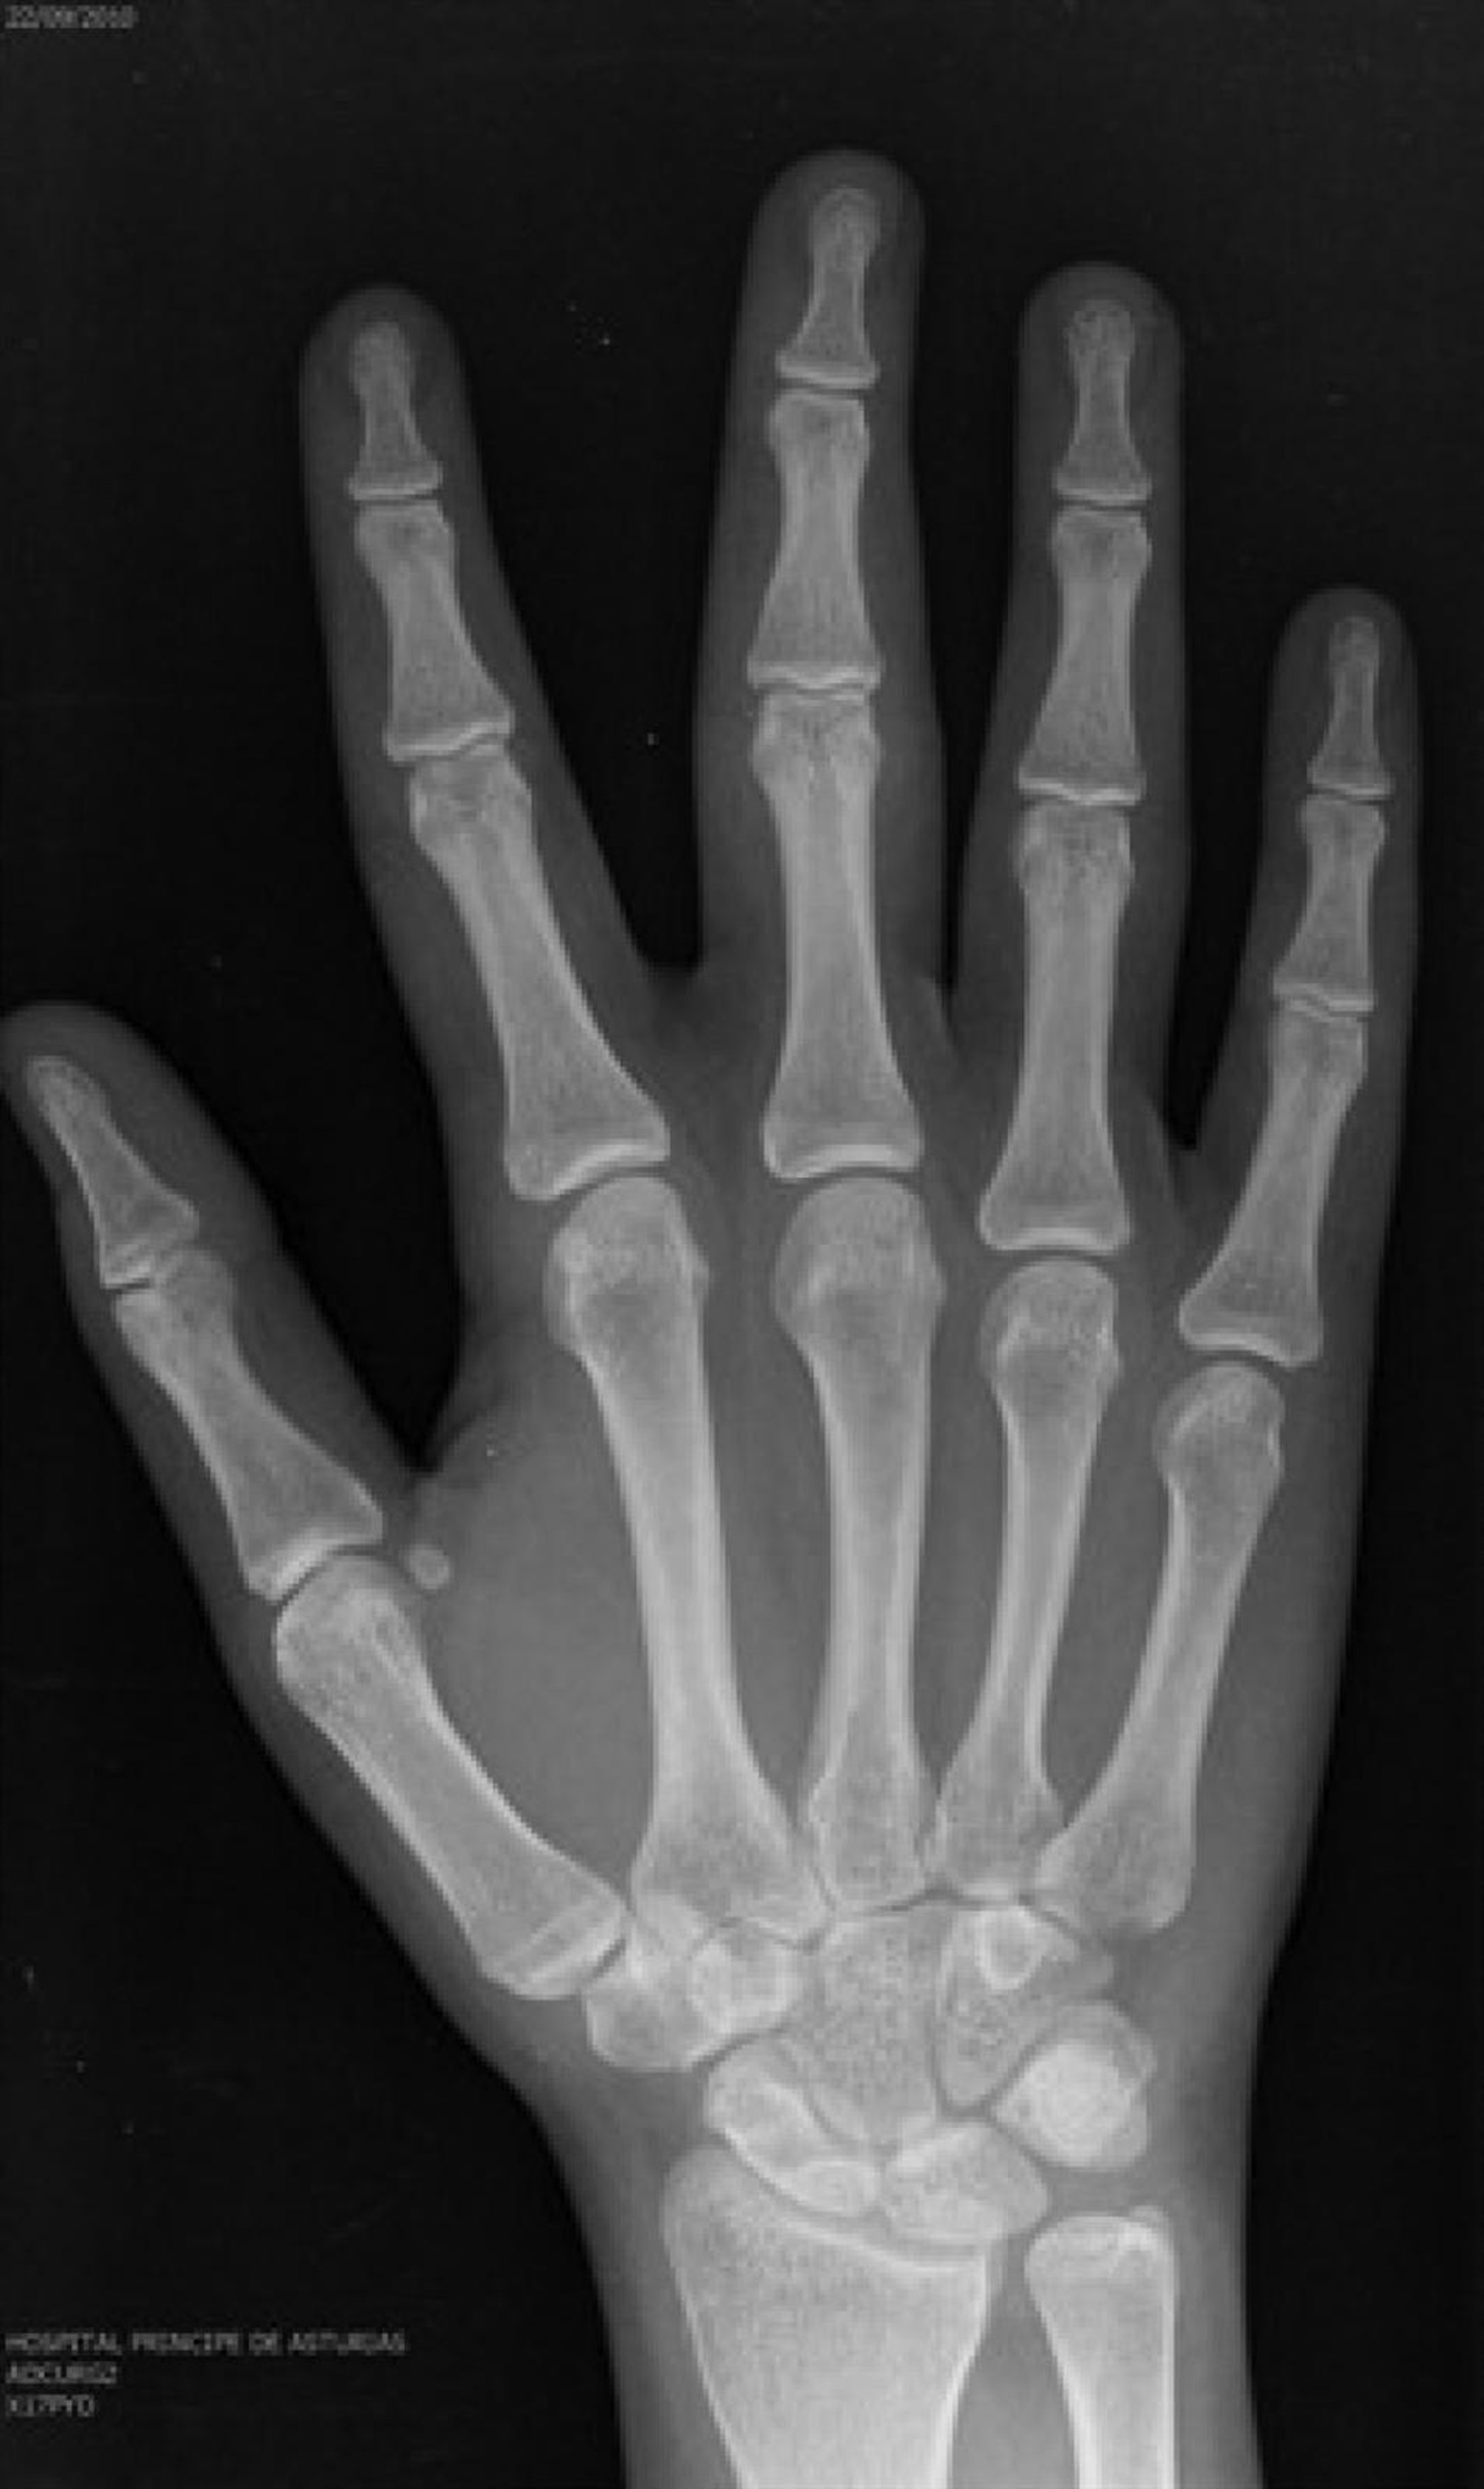

Un inmigrante puede ser adulto o adolescente en función del lugar donde le examinen, según denuncia en un informe el Defensor del Pueblo, en el que expone el caso de un joven al que sometieron a pruebas radiológicas para determinar la edad ósea en hospitales de Valencia, Andalucía y Madrid, siendo los resultados diferentes en un intervalo de dos semanas, o el de una mujer subsahariana de raza negra declarada mayor de edad en menos de 24 horas siguiendo criterios para varones blancos.

La falta de rigor científico en los procedimientos para determinar la edad de los menores extranjeros no acompañados es una de las conclusiones de este trabajo, en el que se advierte de que en muchos casos les someten exclusivamente a una única prueba, cuando los expertos indican que el proceso de estimación debe ser el resultado del trabajo de diversos especialistas --radiólogos, forenses, médicos y psicólogos, entre otros--.